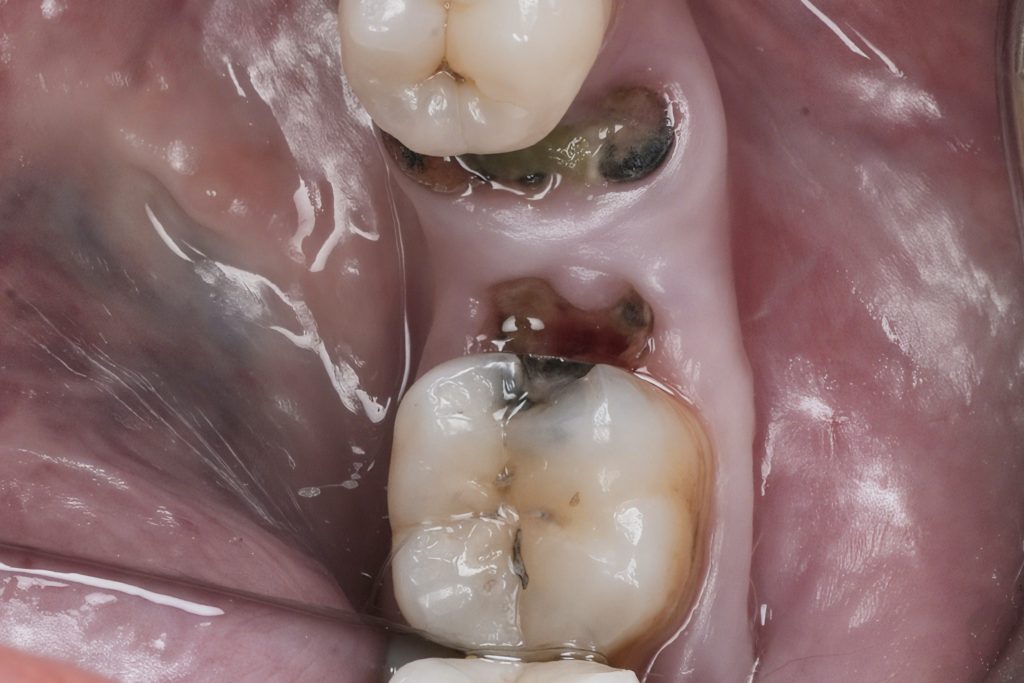

Rubber-dam isolation achieved using heavy-gauge dam and pre-curved clamps ensuring optimal gingival retraction. Under magnification, all caries and unsupported enamel were removed while maintaining pericervical dentin (Fig 3).

Fig 3: Rubber-dam isolation and caries removal under magnification.